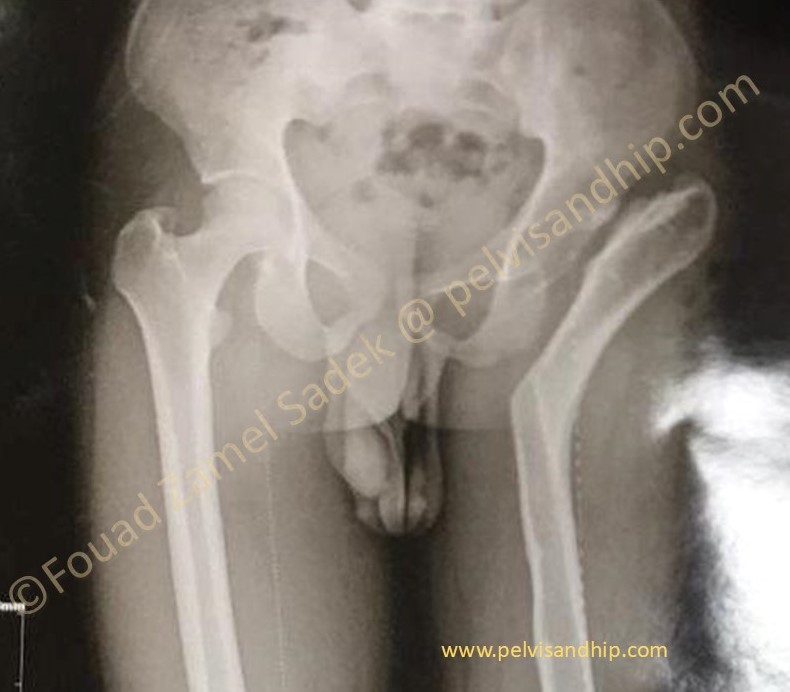

Case 13: 22 years old Male presenting 7 years after a pelvic support osteotomy please click on the picture for further study of this case)